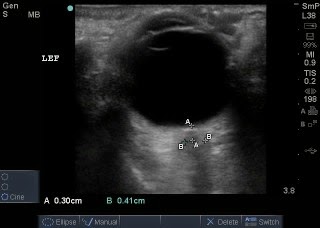

This is an ultrasound image of the normal eye showing the small black stripe posterior to the globe (bottom of image), which is the optic nerve.

Optic Nerve Sheath Diameter (ONSD) measured: Example of measuring the optic nerve sheath. A is the initial measurement going down the length of the nerve, 3mm. B is the width of the nerve sheath, 4.1mm (normal).